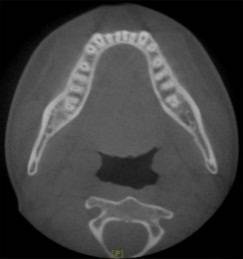

放射检查:一般包括X线头影测量片、曲面体层片和CBCT(锥束CT)。有时还包括其他放射检查,比如螺旋CT等。通过放射检查,医生能够看到骨骼及牙齿的形态、位置及发育状况,以及是否有牙体、根尖周、牙周疾病等,从而评估是否需要正畸治疗、进行何种治疗。

(摘自“第三章第一节正畸的基本知识”)

头影测量片(上)、曲面体层片(中)和锥束CT(下)